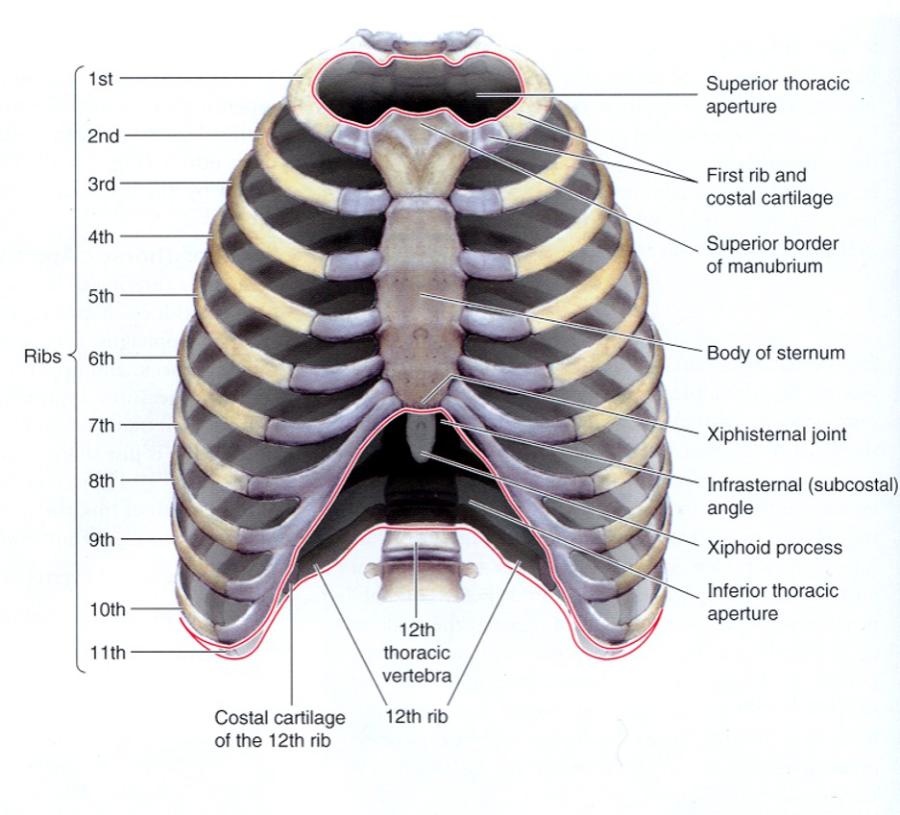

- Jugular (sternal) notch (JN)

- Sternal angle (SA)

- 2ND rib

- Intercostal spaces (ICS)

- Intercostal spaces 2 - 6

- costal margin (CM)

- subcostal angle (SCA)

look at picture

name the 3 bones of the thoracic wall?

their function?

- Bones of the thoracic wall = ribs, thoracic vertebrae and sternum

- Function – protect thoracic content…heart, lung, blood vessels, esophagus, etc…

Identify the structures of the sternum

- Manubrium

- Sternum (body)

- Sternal angle

- Jugular notch

- Articular sites for clavicle

- Xiphoid

M up top

Body in middle

X point at bottom

jugular notch at top

two facets next to that is articulation sites for the clavicle

identify the sub-divisions of the ribs (true, false and floating) and describe them?

- True (1-7) – attach “directly” to sternum

- False (8-10) – attach “indirectly” to sternum thru cartilage

- Floating (11-12) – do not attach to the sternum AKA dont even make their way around

show what the superior thoracic aperture and inferior thoracic aperture are?

notice how in the first picture the esophagus and trachea, nerves and BV's are popping through